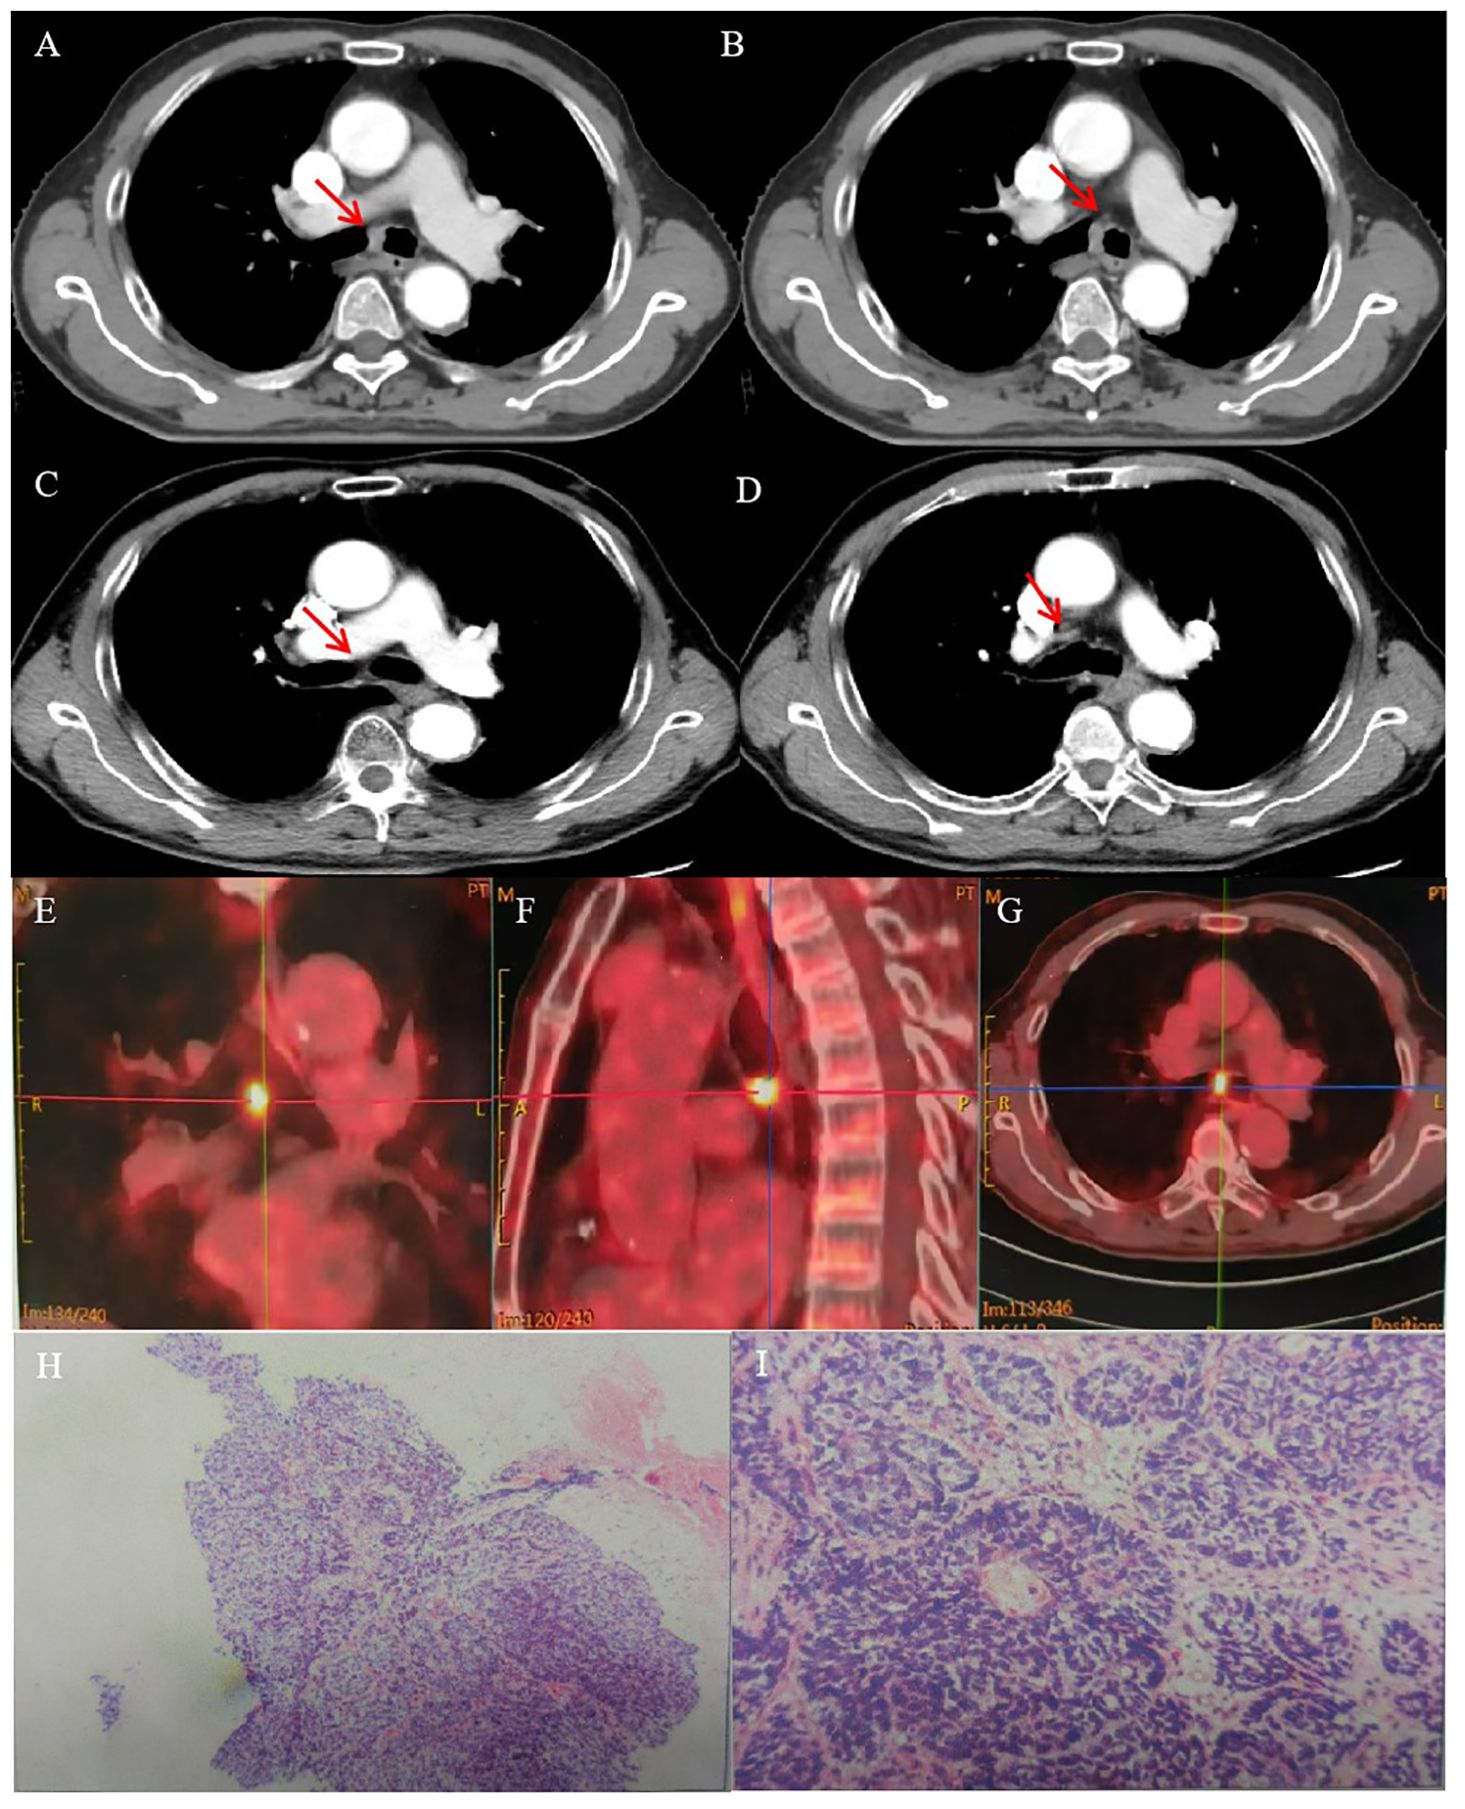

A 74-year-old man presented with a 2-month history of intermittent coughing, expectoration, and blood-tinged sputum, without fever, dyspnea, and thoracalgia. His past medical history was characterized by a kidney stone treated with extracorporeal lithotripsy and arrhythmia (sinus arrhythmia has persisted for over 50 years without oral medication treatment). An enhanced chest computed tomography (CT) showed an opacity at the tracheal carina (Figures 1A, B). To verify the nature of the lesion, fiberoptic bronchoscope examination and histopathologic biopsy were performed at a local hospital. The fiberoptic bronchoscope was used to verify the lesion, and the pathological diagnosis of the biopsy was squamous cell carcinoma with focal neuroendocrine (NE) marker expression (Figures 1H, I). Immunohistochemistry showed the following results: CD56 (+), CgA (-), CK (+), CK5/6 (+), CK7 (+), ki-67 (+, 50%), P40 (+), Syn (–), TTF-1 (–), and NapsinA (–). Then, the patient visited our hospital, and a positron emission tomography (PET)/CT scan revealed the thickness of the tracheal carina, with a maximum diameter of 11 mm and showing a strong 18F-fluorodeoxyglucose (18-FDG) uptake (SUVmax 10.6) without distant metastasis (Figures 1E–G). In terms of laboratory examination, the results of routine blood and urine examinations were normal, as were those of the biochemistry examination. Based on the results above, the patient was diagnosed with tracheal SCC. The American Joint Committee on Cancer (AJCC) does not have TNM stage definitions for tracheal tumors; however, the stage was cT4N0M0, stage IIIA according to AJCC for lung cancer staging or cT1N0M0, stage I according to the classification proposed by Bhattacharyya (13).

Figure 1. CT images and RT target of case 1 patient. (A, B) Computed tomography (CT) revealed a tracheal lesion at the carina. (C, D) The lesion disappeared 2 months after RT. (E–G) PET/CT revealed the thickness of the trachea of carina with a maximum diameter of 11 mm and showing strong 18F-fluorodeoxyglucose (18-FDG) uptake (SUVmax 10.6). (H, I) Photomicrograph of case 1 patient with primary tracheal carcinoma. The neoplasm showed the characteristic features of PTC. (A) ×100. (B) ×400.

The patient had no obvious side effects during RT, only mild nausea and fatigue. He recovered well after RT without chemotherapy. At 2 months later, the CT result showed that the trachea was unobstructed and that there was no recurrence (Figures 1C, D). At 6 months after RT, he reported no blood-tinged sputum, and his body movement had returned to normal. The authors confirm that written informed consent was provided by the patient for the publication of this case report and the inclusion of accompanying images.